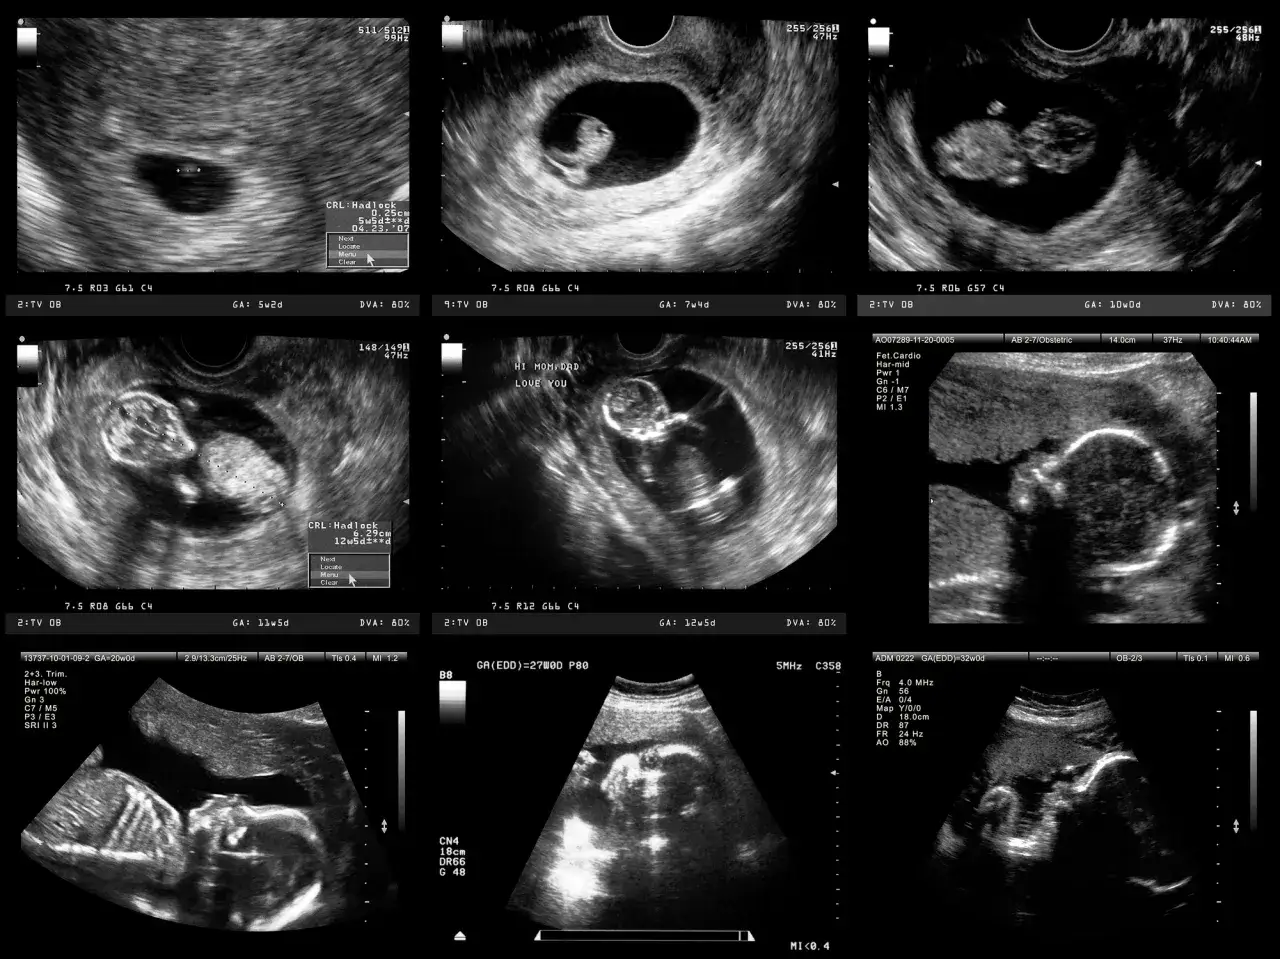

- USG połówkowe (między 18. a 22. tygodniem) to kluczowe badanie, które pozwala szczegółowo ocenić rozwój dziecka i sprawdzić jego anatomię.

Okres między 18. a 22. tygodniem ciąży to czas na jedno z najważniejszych badań prenatalnych USG połówkowe, często nazywane również genetycznym lub anatomicznym. To nie tylko okazja, by zobaczyć swojego maluszka w całej okazałości, ale przede wszystkim kluczowe badanie diagnostyczne. Pozwala ono na szczegółową ocenę rozwoju dziecka i wykrycie ewentualnych wad wrodzonych. Dla mnie, jako przyszłej mamy, to zawsze moment pełen emocji i ulgi, kiedy widzę, że wszystko jest w porządku.

Od stóp do głów: Co dokładnie sprawdza lekarz podczas USG?

Podczas USG połówkowego lekarz bardzo dokładnie ogląda Twoje dziecko, analizując każdy jego fragment. To prawdziwy przegląd "od stóp do głów":

- Mózg: Ocena struktur mózgowia, wykluczenie wad rozwojowych.

- Serce: Analiza budowy i funkcji serca, sprawdzenie przepływów krwi to niezwykle ważne, ponieważ serce jest jednym z najczęściej dotykanych wadami narządów.

- Nerki: Sprawdzenie obecności obu nerek i ich prawidłowej budowy.

- Kręgosłup: Ocena ciągłości i prawidłowego uformowania kręgosłupa.

- Kończyny: Sprawdzenie wszystkich kości kończyn górnych i dolnych, ich ruchomości oraz liczby palców.

- Inne narządy: Ocena pozostałych narządów wewnętrznych, takich jak żołądek, pęcherz moczowy, jelita, pod kątem wad wrodzonych.

Czy na tym etapie poznam już płeć dziecka?

Tak! W trakcie badania USG połówkowego, dzięki zaawansowanej technologii i zazwyczaj bardzo dobrej wizualizacji, z dużą dokładnością można określić płeć dziecka. Oczywiście, pod warunkiem, że maluszek odpowiednio się ułoży i pozwoli lekarzowi na wyraźne zobaczenie niezbędnych struktur. To często jeden z najbardziej wyczekiwanych momentów dla przyszłych rodziców!